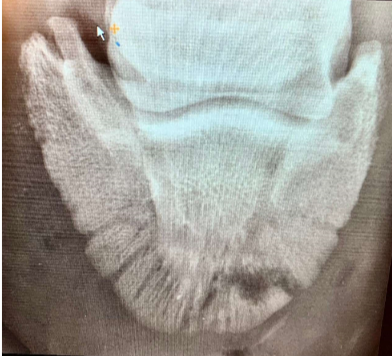

• Osteolysis can be seen in the radiolucency, the main circle is where the needle penetrated. The bone has separated from the pedal bone (sequestrum) and these radiolucent lines are called the involucrum